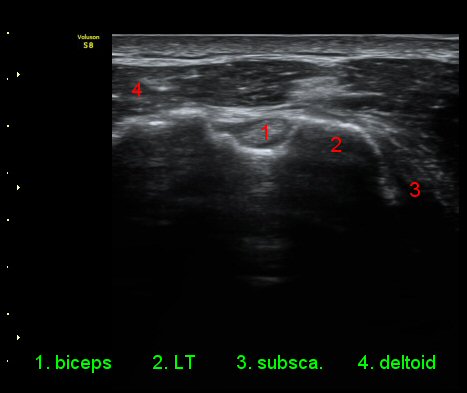

ÀÌµÎ¹Ú±Ù°Ç È¾´Ü¸é°Ë»ç¿¡¼­ °ÇÁÖÀ§¿¡ ¼Ò·®ÀÇ ¼ö¾×Àú·ù¿Í Á¡¾×³¶³» ¾×Àú·ù°¡ °üÂûµÈ´Ù(»çÁø 1, 2).